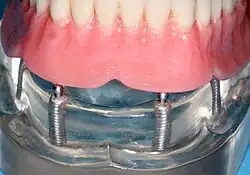

Четыре нижних имплантата для сохранения полного протеза с абатментами Новалок

Нижняя часть зубного протеза; корпус подходит как шарик и гнездо для протеза